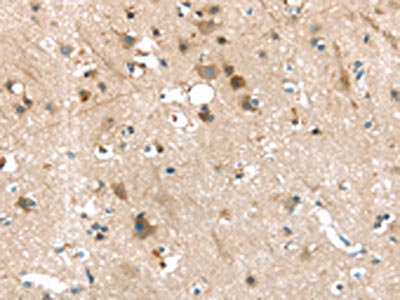

The image on the left is immunohistochemistry of paraffin-embedded Human brain tissue using CSB-PA576176(P2RY2 Antibody) at dilution 1/30, on the right is treated with synthetic peptide. (Original magnification: ×200)